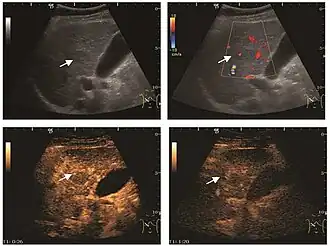

HCC appearance on 2D ultrasound is that of a solid tumor, with imprecise delineation, with heterogeneous structure, uni- or multilocular (encephaloid form). An "infiltrative" type is also described which is difficult to discriminate from liver nodular reconstruction in cirrhosis. Typically HCC invades liver vessels, primarily the portal veins but also the hepatic veins . Doppler examination detects a high speed arterial flow and low impedance index (correlated with described changes in tumor angiogenesis). The spatial distribution of the vessels is irregular, disordered. CEUS examination shows hyperenhancement of the lesion during the arterial phase. During the portal venous phase there is a specific "wash out" of ultrasound contrast agent (UCA) and the tumor appears hypoechoic during the late phase. Poorly differentiated tumors may have a stronger wash out leading to an isoechoic appearance to the liver parenchyma during portal venous phase. This appearance was found in approx. 30% of cases. The described changes have diagnostic value in liver nodules larger than 2 cm.